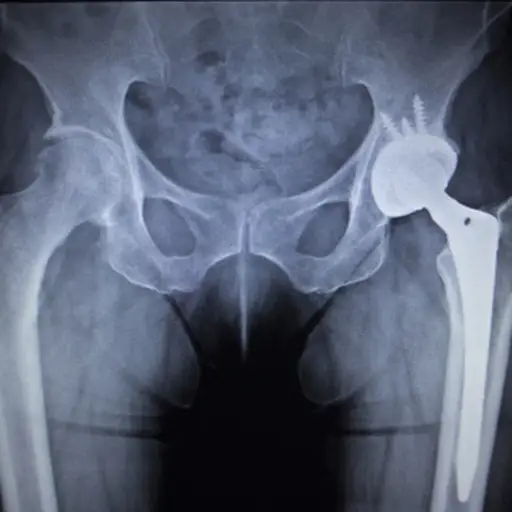

沃德博士说,手术不经常使用,并且通常不用于脊柱或骶髂关节。“没有手术可以停止疾病进展。大约10%至15%的人的髋关节炎足够严重,以导致髋关节替换作为长期后果。很少有人碰巧与弯曲的姿势向下融合,有一个弯曲的姿势,有一个非常广泛的脊柱矫正程序,可以为此进行 - 但它通常不是一个选择。“